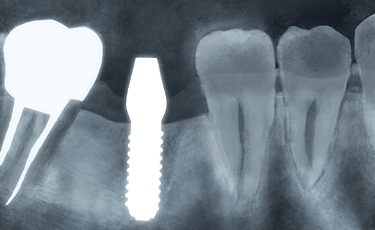

歯を失ったときの治療法には“ブリッジ、入れ歯、インプラント”があげられます。

ブリッジ ![]() |

失った歯の部分の左右の歯を削り、